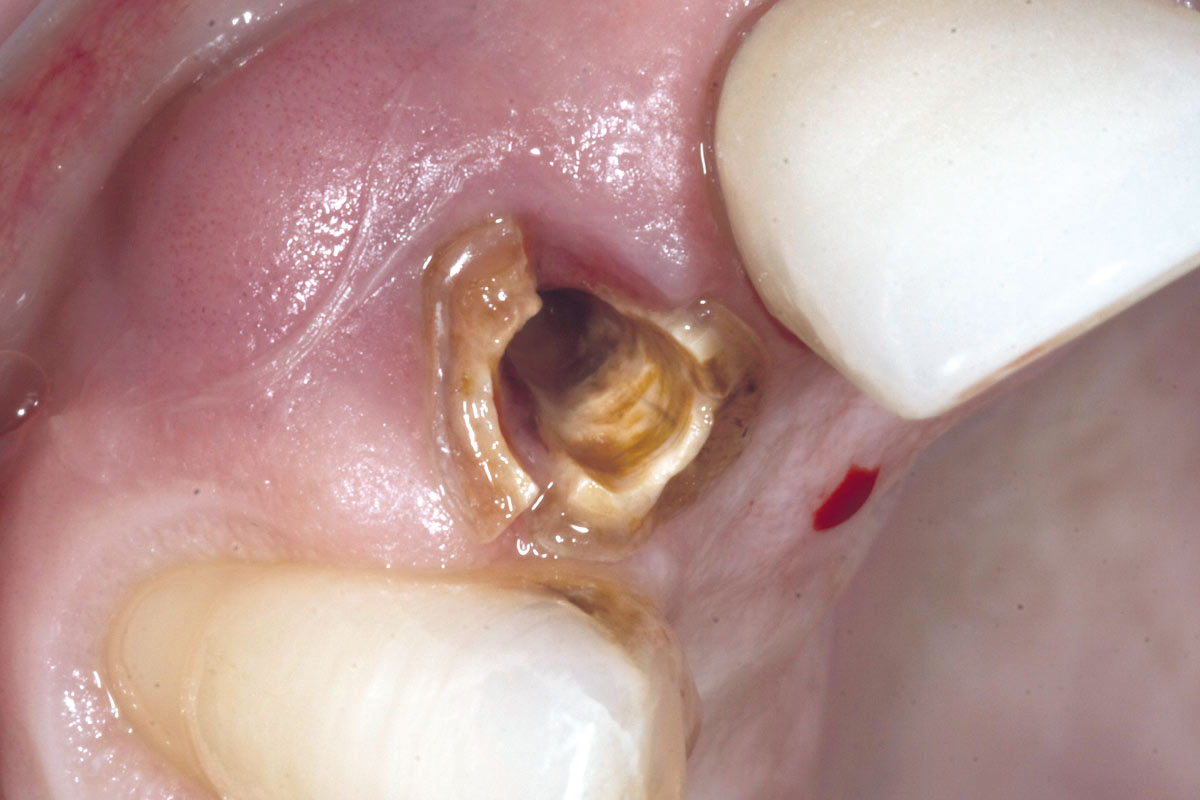

3/19 - Fracture of tooth while extractionBone augementation with maxresorb® - Dr. R. Cutts